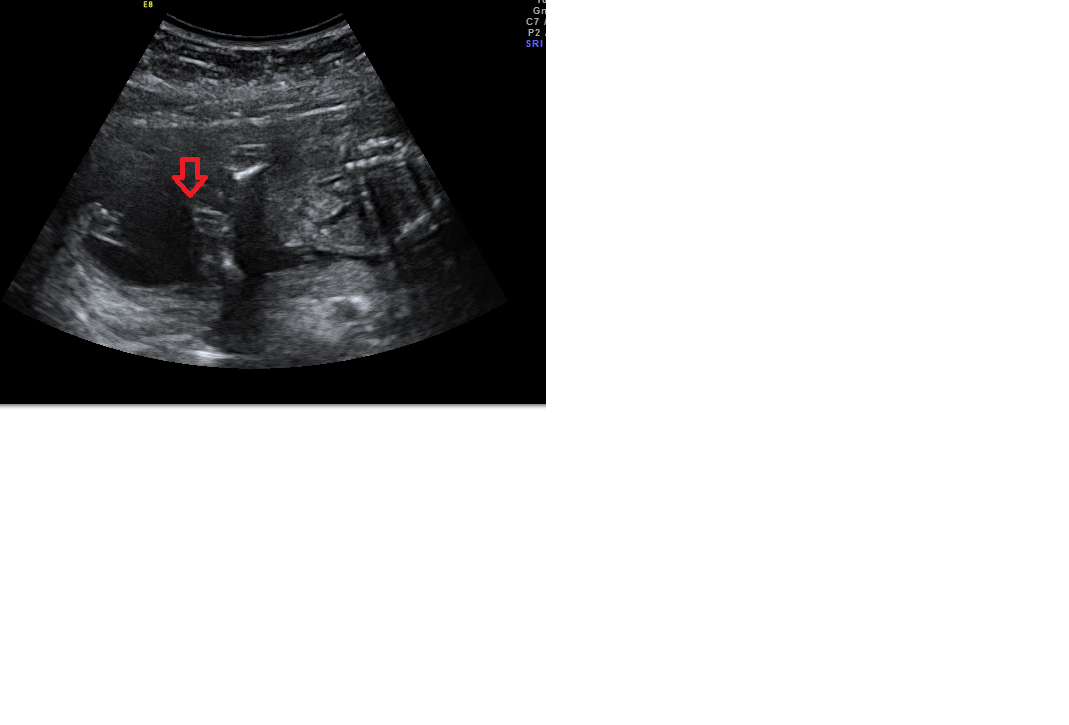

červenou šipku na šedočerném poli...

Je to teda videt hur, ale rekla bych holkA

Holčička je tam kávove zrnko

Holka...zrno jako Brno

Holčička